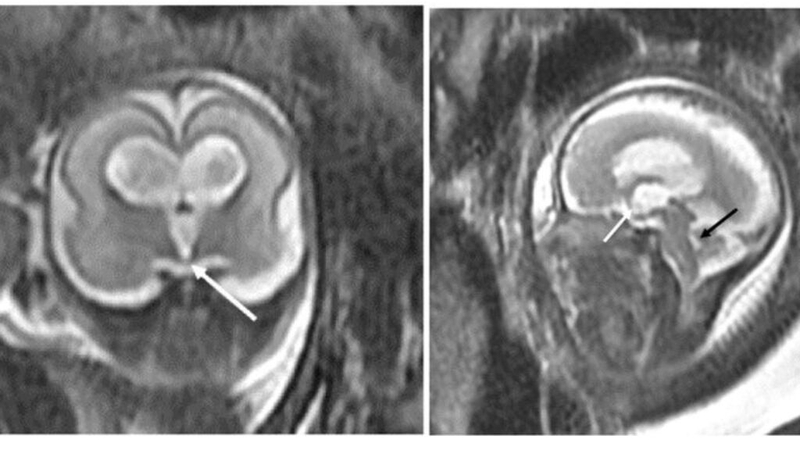

Chụp MRI não cho thai nhi mang lại nhiều lợi ích quan trọng. Qua quy trình này, các bác sĩ có thể xem xét và đánh giá sự phát triển của não thai nhi một cách chi tiết. Điều này giúp phát hiện sớm các vấn đề tiềm ẩn và can thiệp kịp thời để đảm bảo sự phát triển toàn diện của thai nhi. Chụp MRI không sử dụng tia X hay tia cực tím, mà thay vào đó sử dụng sóng từ và từ trường, giúp giảm nguy cơ phản ứng phụ đối với thai nhi.

Việc chụp MRI não cho thai nhi có tầm quan trọng lớn trong việc đánh giá sự phát triển và sức khỏe của thai nhi. Dưới đây là một số tầm quan trọng của việc chụp MRI não trong quá trình mang thai:

Tổng quan, chụp MRI não cho thai nhi đóng vai trò quan trọng trong việc đánh giá sự phát triển và sức khỏe của thai nhi. Qua việc cung cấp thông tin chi tiết về não và tình trạng sức khỏe tổng thể, nó hỗ trợ quá trình chăm sóc và can thiệp kịp thời để đảm bảo sự phát triển toàn diện và sức khỏe tốt cho thai nhi.